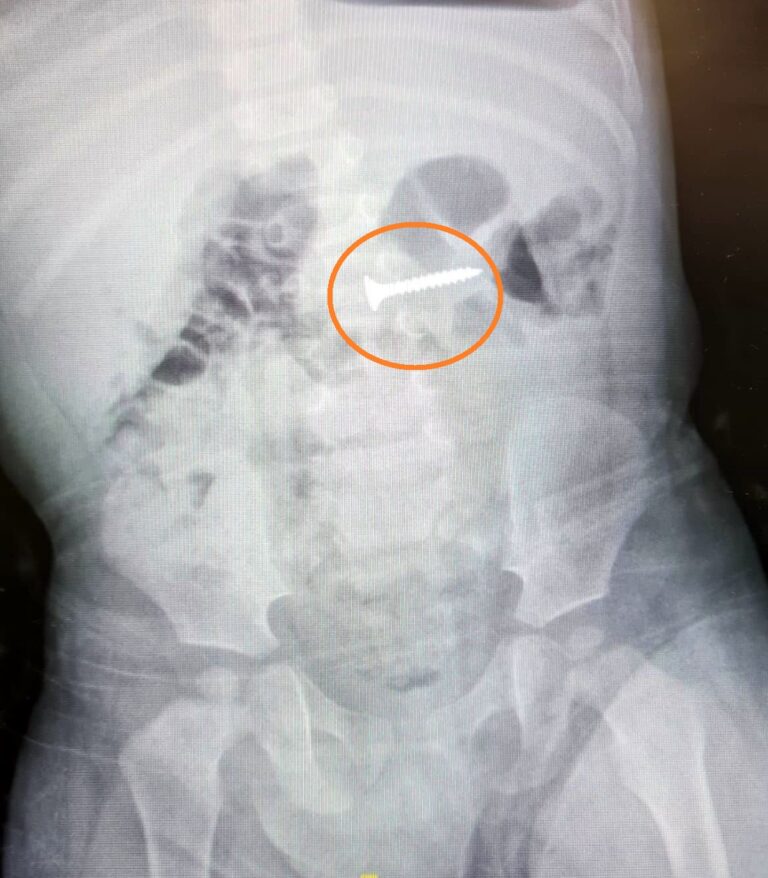

בבית חולים פדה-פוריה חילצו בורג מבטנו של פעוט

הודות לערנות של האם נמנעה סכנת חיים לפעוט שבלע בורג. הבורג שתוך זמן קצר הגיע לתרסריון חולץ בהצלחה ע"י ד"ר אבי און, מנהל מכון גסטרו ילדים, במרכז הרפואי פדה-פוריה